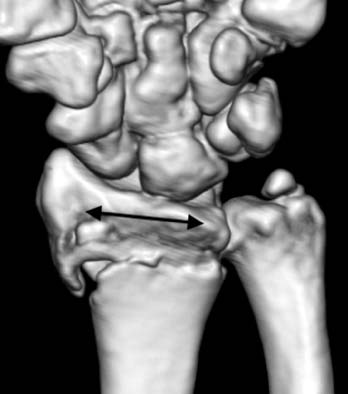

Fig. 6

The arrow indicates transverse ridge line of the distal radius.

Fig. 6 The arrow indicates transverse ridge line of the distal radius.